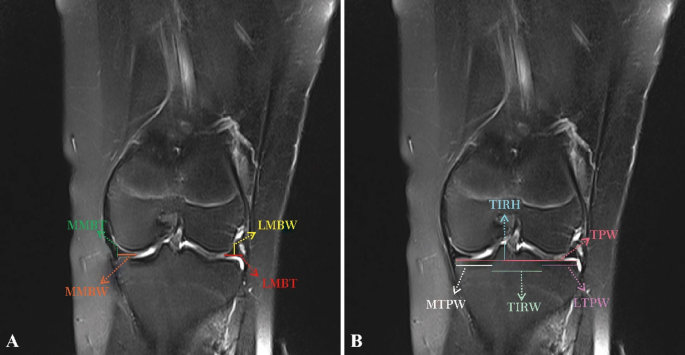

On the coronal images of the T2WI sequence, the measurements were as follows: the lateral meniscal body thickness (LMBT), the lateral meniscal body width (LMBW), the medial meniscal body thickness (MMBT), the medial meniscal body width (MMBW), the tibial plateau width (TPW), the lateral tibial plateau width (LTPW), the medial tibial plateau width (MTPW), the tibial intercondylar ridge width (TIRW), and the tibial intercondylar ridge height (TIRH) (Fig. 2). On the sagittal images of the T2WI sequence, the measurements were as follows: the lateral meniscal anterior horn thickness (LMAT), the lateral meniscal anterior horn width (LMAW), the lateral meniscal posterior horn thickness (LMPT), the lateral meniscal posterior horn width (LMPW), the lateral meniscal sagittal diameter (LMSD), the medial meniscal anterior horn thickness (MMAT), the medial meniscal anterior horn width (MMAW), the medial meniscal posterior horn thickness (MMPT), the medial meniscal posterior horn width (MMPW), and the medial meniscal sagittal diameter (MMSD) (Figs. 3 and 4). Although the study performed measurements on T2WI, the researchers reviewed T1WI and fat-suppressed sequences to confirm meniscal boundaries and to exclude abnormalities.

Measurements in the coronal position of MRI.